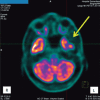

Traumatic brain injury (TBI) is a major cause of lifelong disability and death worldwide. Sport-related traumatic brain injury is an important public health concern. The purpose of this review was to highlight the importance of sport-related concussions. Concussion refers to a transient alteration in consciousness induced by external biomechanical forces transmitted directly or indirectly to the brain. It is a common, although most likely underreported, condition. Contact sports such as American football, rugby, soccer, boxing, basketball and hockey are associated with a relatively high prevalence of concussion. Various factors may be associated with a greater risk of sport-related concussion, such as age, sex, sport played, level of sport played and equipment used. Physical complaints (headache, fatigue, dizziness), behavioral changes (depression, anxiety, irritability) and cognitive impairment are very common after a concussion. The risk of premature return to activities includes the prolongation of post-concussive symptoms and increased risk of concussion recurrence.